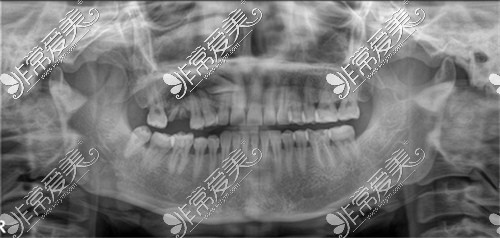

今天有点工作影响了,一直在打电话,助理小姐姐和医生耐心的等待我处理完,助理小姐姐好温柔哦,带我去拍牙片,动作都很温柔,轻轻的帮我穿好像防护服一样的衣服。

拍好牙片,小姐姐耐心的跟我讲了一下牙齿的情况,边聊边带我去医生的诊室。